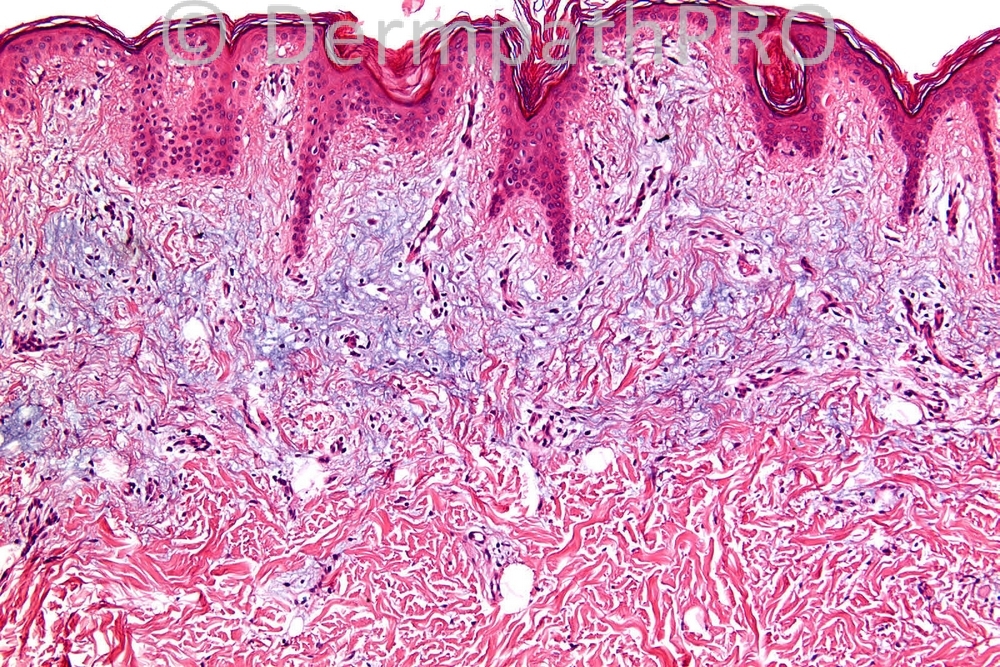

Male 13 years, yellowish plaque - cobble stone surface on back: lumbar. ?Xanthogranulomas. ?Seb naevus. ?Connective tissue naevus.